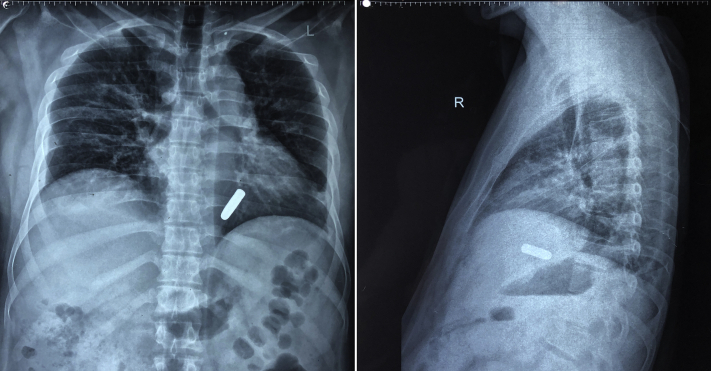

The chest radiograph showed a bullet shadow inside the cardiac silhouette with the tip pointing away from the direction of entry wound, a finding suggesting that the bullet had ricocheted from the thoracic wall (Figure 2). The electrocardiogram showed diffuse ST-segment elevation and PR-segment depression suggestive of either pericarditis or myocardial contusion (Figure 3). Hemoglobin and hematocrit values were 14 g/dl and 42.4%, respectively. The total leukocyte count and renal parameters were normal. Cardiac troponin I was elevated (1.32 ng/ml). The patient underwent a nongated contrast enhanced computed tomography (CECT) scan of the thorax to localize the bullet. However, prominent beam-hardening artifacts caused by the metallic bullet prevented exact localization, and the site of the bullet was deemed to be probably intracardiac (Figure 4).

Figure 2.

Chest Radiographs in the Anteroposterior and Lateral Views Showing an Intrathoracic Bullet